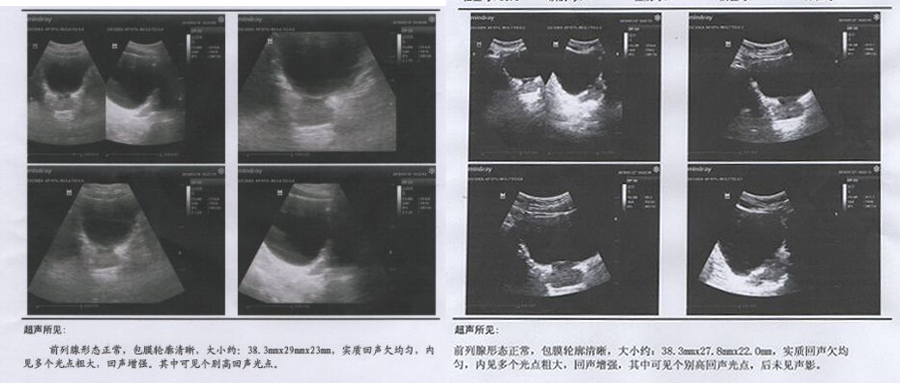

在前列腺B超检查单上,第三重要的就是回声。

超声波在检查中会穿过腺体,所以健康的腺体不会把声波反弹回来,但病灶出现后,声波会被病灶反弹回来,形成回声。

很多病友的检查显示:回声不均匀。

这是前列腺慢性病变初期在B超下的成像。前列腺慢性病变由腺体局部的神经末梢和毛细血管坏死形成,在病变初期,病灶小而且非常柔软,在超声检查时就体现为回声不均匀。

当纤维化病灶形成后,B超检查时就形成了回声,回声越强,说明病灶硬度越硬,病变越严重。

很多患前列腺钙化的病友会看到他们的检查单上显示强回声,有的病友则形成了强回声光点,这代表着他们的病灶已经很硬,形成了钙化病灶。

有的病友的前列腺钙化病灶已经形成了很多年,面积不小,检查的时医生会标示出病灶的尺寸,让治疗的医生和病友都清楚知道自己的病灶大小,方便治疗和用药。